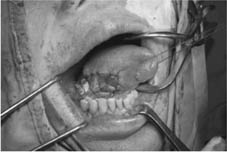

病例二

舌惡性腫瘤

腫瘤切除後之傷口

以冷凍乾燥異體肌膜修補傷口

傷口施以壓迫一週

傷口癒合良好

舌頭形狀及功能無太大影響